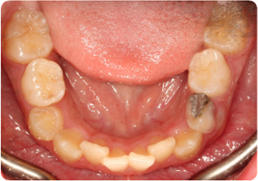

Each case shows the front view and an arch or side view, before and after BioLign Method-guided treatment.

All cases treated within 6–12 months.

Misaligned lower arch corrected with coordinated expansion